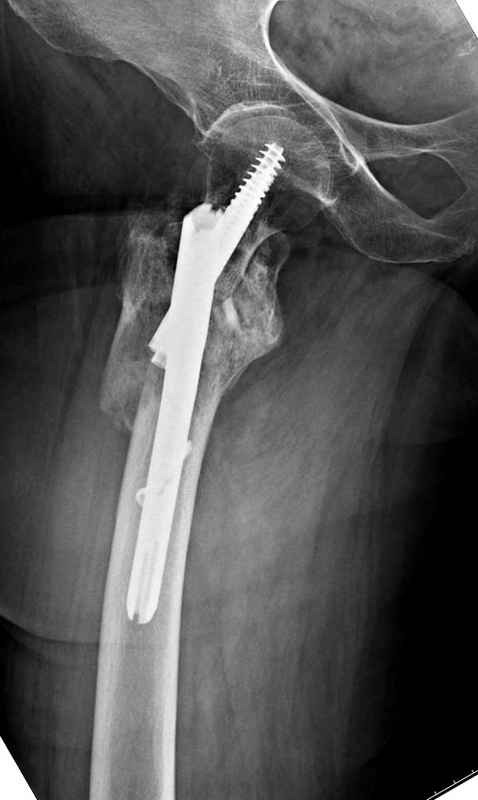

Здесь 83 года, травма в результате падения